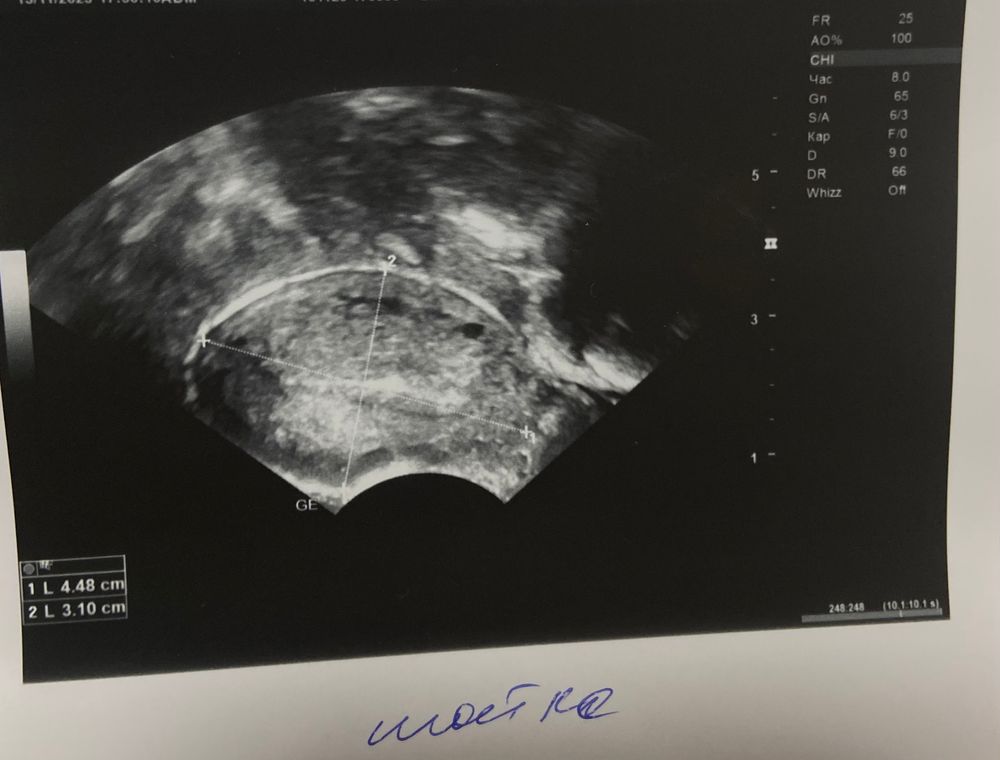

Сходила на узи, похоже на плодное яйцо?

Если нет, то что это может быть?

А посмотрев дома на снимок, я задумалась о плодном яйце…

Плодное яйцо черного цвета будет в матке на узи. Если оно и есть, то вот этот черный кругляшок справа ниже. Погуглите узи на раннем сроке, как выглядит яйцо.